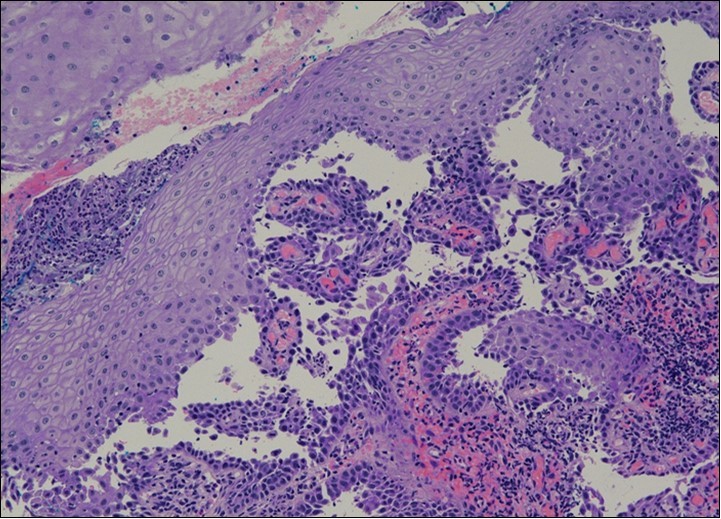

Repeat colposcopy was performed after 6 weeks. This revealed a small ulcerated area at the site of previous biopsy with rolled healing edges, and a separate small ulcer at the 12 o’clock position. (Figure 2a, Figure 2b, Figure 2c) Careful inspection of the buccal mucosa revealed similar ulcers in the left buccal region. (Figure 3)

Figure 2b.Repeat colposcopy (high magnification)

She was discussed at the hospital cyto-pathology conference to clarify the diagnosis. The original cytological smear specimen was reviewed, with features of bi-nucleation and koilocytosis consistent with LSIL. The cervical biopsy was also reviewed, confirming typical features suggestive of cervical pemphigus. (Figure 4a, Figure 4b, Figure 4c)

Figure 4a.Cervical tissue showing intraepidermal and supra-basal blister formation.